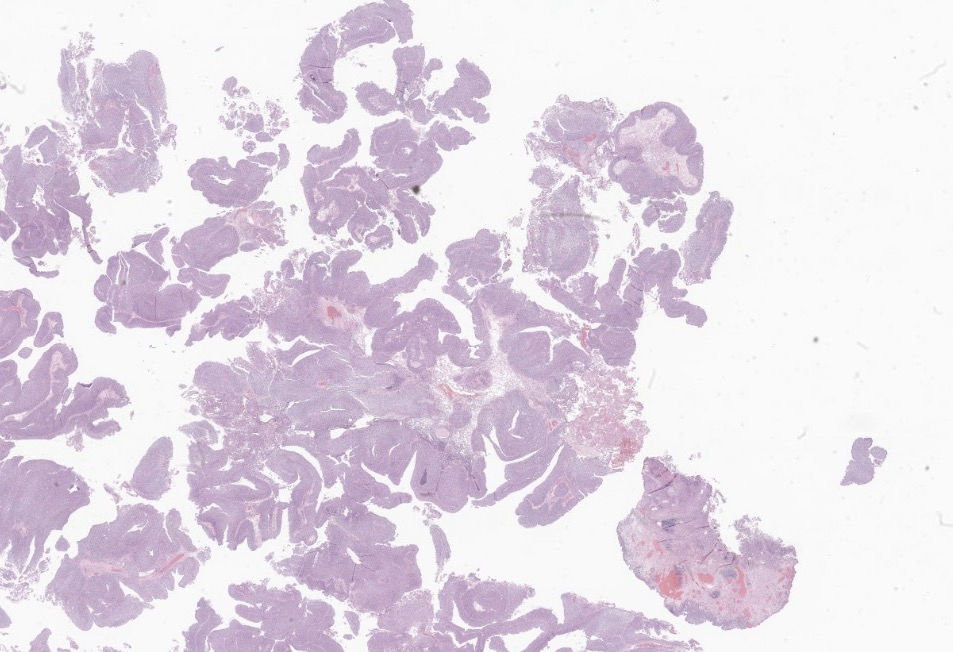

A 70 year old male was found to have a exophtic bladder lesion. TURBT specimen of the lesion is shown below:

The correct answer is non-invasive papillary urothelial carcinoma, low-grade. This could be a highly subjective area. A summary of key features for the differential diagnosis by WHO is shown below:

3.LG: fibrovascular papillary cores or expanded and inverted nests, lined by urothelial cells with (at most) mild cytological atypia and architectural disorder; absence of marked nuclear size variation and hyperchromasia

There is very mild to none loss of polarity in LG

Back to this case, the tumor is definitely thickened, showed maintained polarity, no marked nuclear size variation, and of note mitosis is not part of the grading system although a marked elevation in mitosis should be interpreted cautiously. In this case it's elevated but mostly near basal layer.